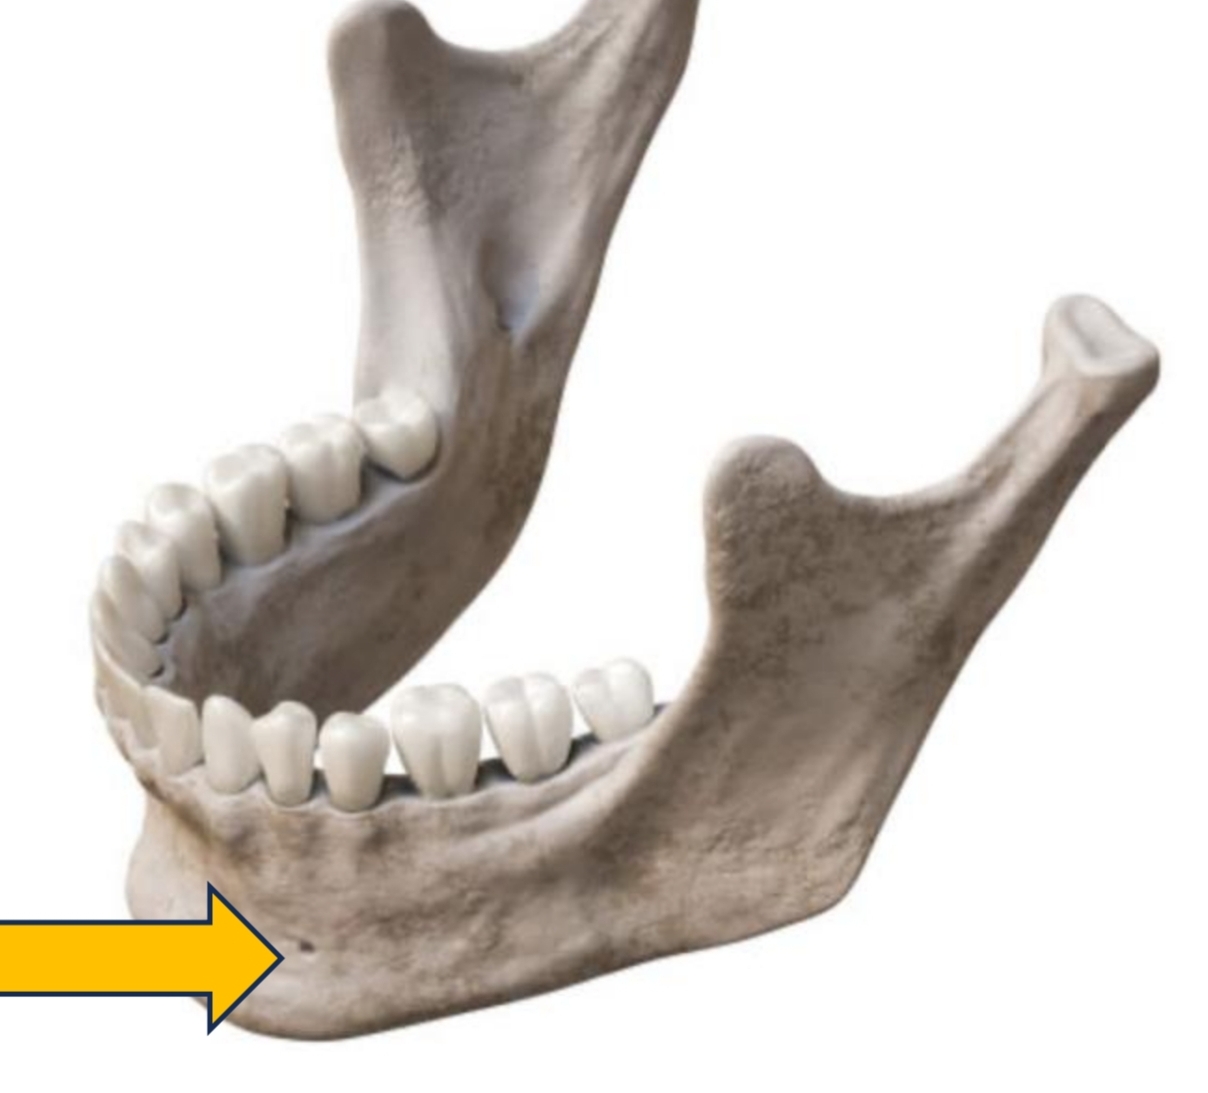

Opening between 1st and 2nd premolars (mental nerve)

Mental Foramen